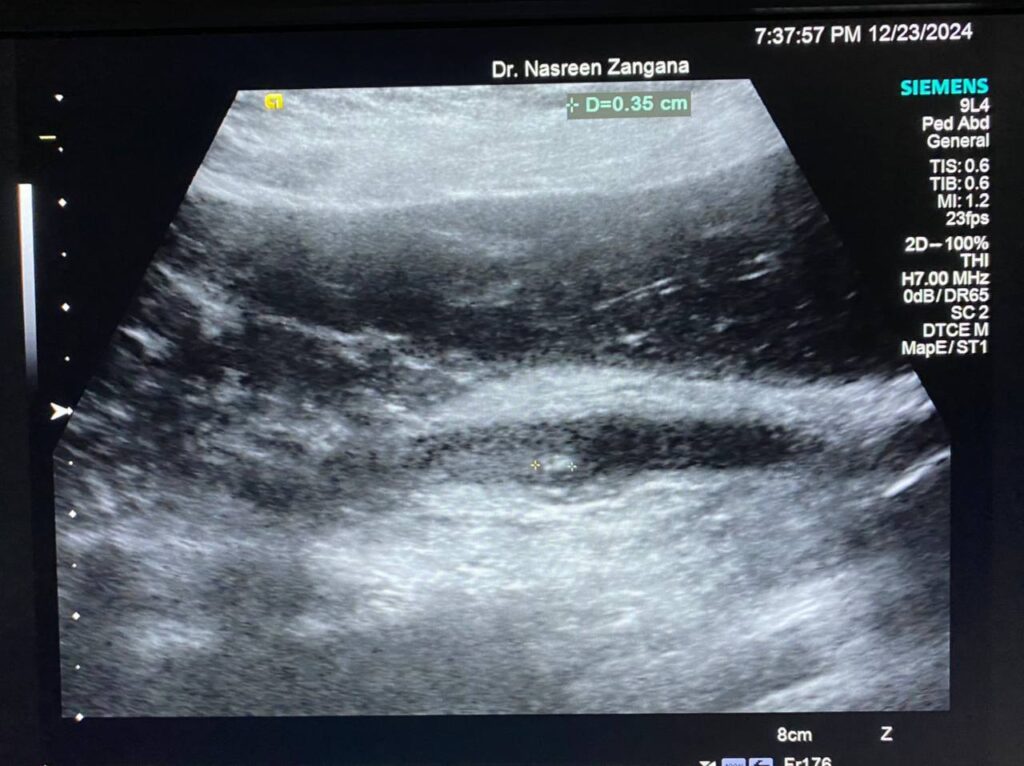

Diffuse dilated common bile duct 7.3mm , with presence of multiple echogenic foci within , the largest 3mm